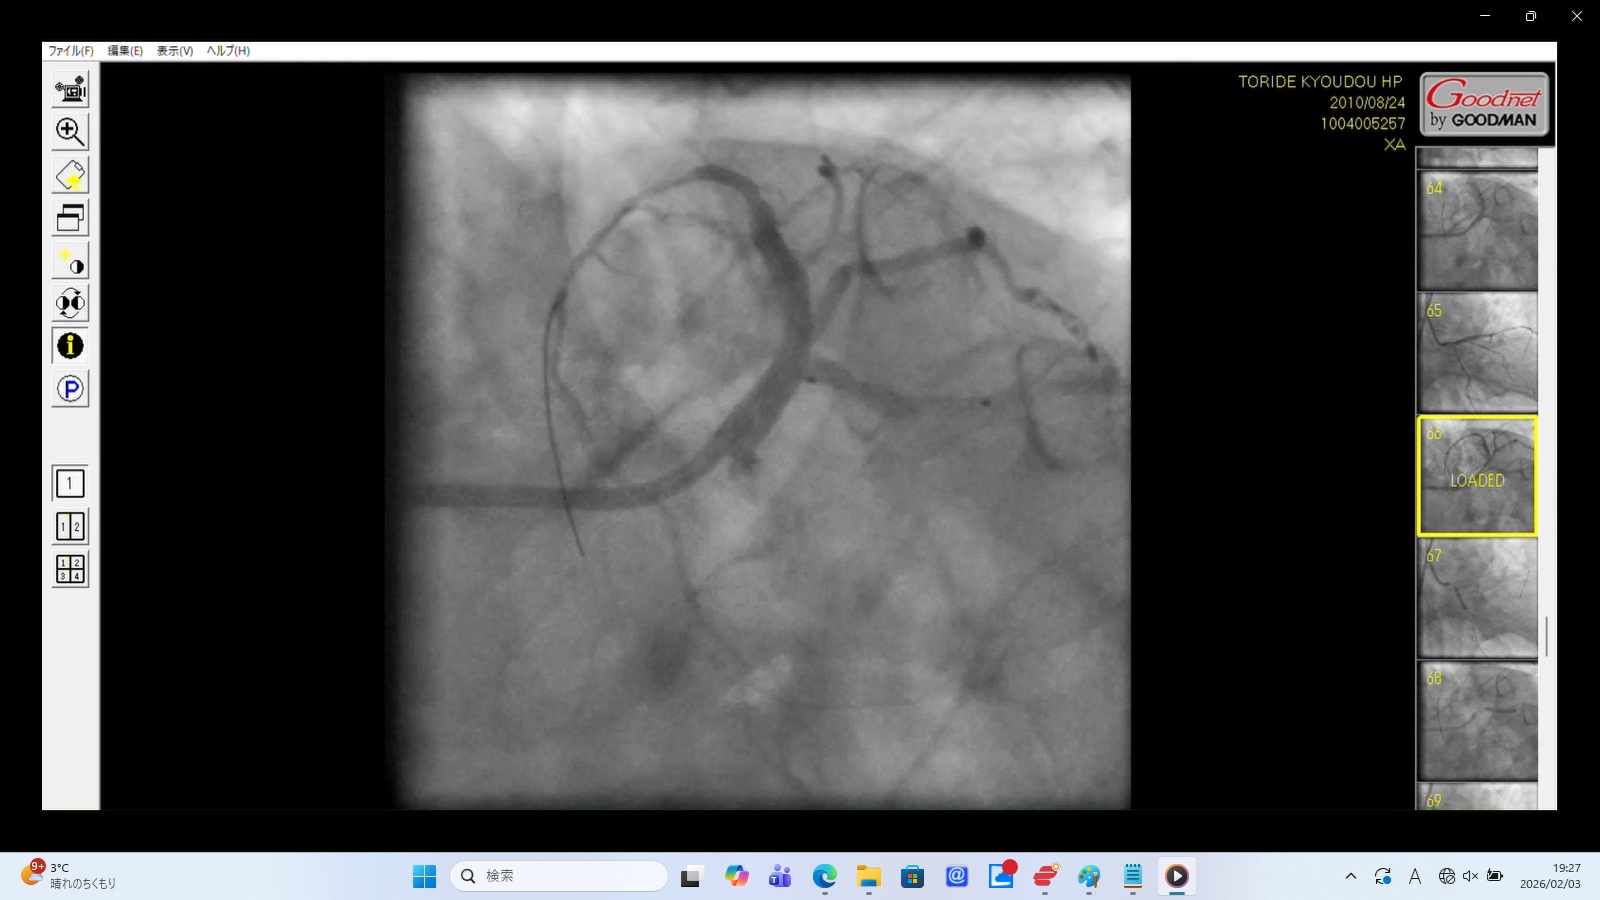

5. XA0066.mp4:左冠動脈前下行枝(LAD)の穿孔・解離(画像をクリックすると動画再生)

画像データ:SHA256:1542152344335685074918BDD718F361F4A50FFC14A76C731E5103BAD01CD211

これらは冠動脈穿孔の典型的な所見。

造影剤の漏出: 画像の下の方がやや黒く染まっており、血管外に漏出した造影剤が下の方に貯留している。これは血管壁が破れ、心嚢内へ血液と造影剤が漏れ出している決定的な証拠。

血流の途絶: 左冠動脈主幹部入口部で造影剤が跳ね返されるのは、左冠動脈主幹部解離・損傷に伴う閉塞を示す重大な所見。